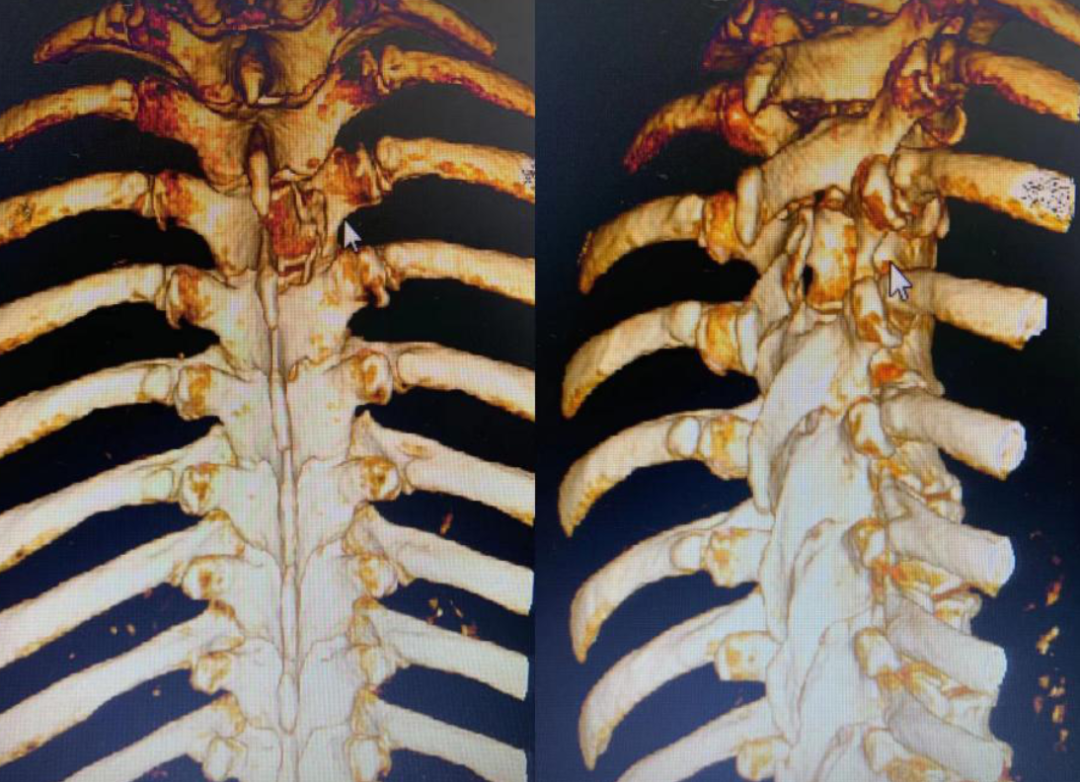

手术时,医生将病人的三维CT图像导入机器人图像系统,主刀医生在机器人系统的计算机上,用鼠标规划好在脊椎椎板上开窗的最小边界和最佳斜率方向,路径边界避开了重要的结构并保留脊柱关节突;随后,启动机器人的机械臂,自动精确走位到该边界,利用携带的磨钻直接在脊椎上开一小窗。然后,医生在显微镜下用显微外科技术打开脊髓神经的硬膜,完整切除肿瘤,该肿瘤为钙化性脊膜瘤。

该手术方法的意义是,医生创新设计了一种从“定点到定点连续移动”的机械臂指令,实现用最小的椎板开窗,保留关节突等重要结构,避免了使用内固定。且术中无需放置引流管,让皮肤手术切口缩小到2.5厘米,病人康复时间加快。